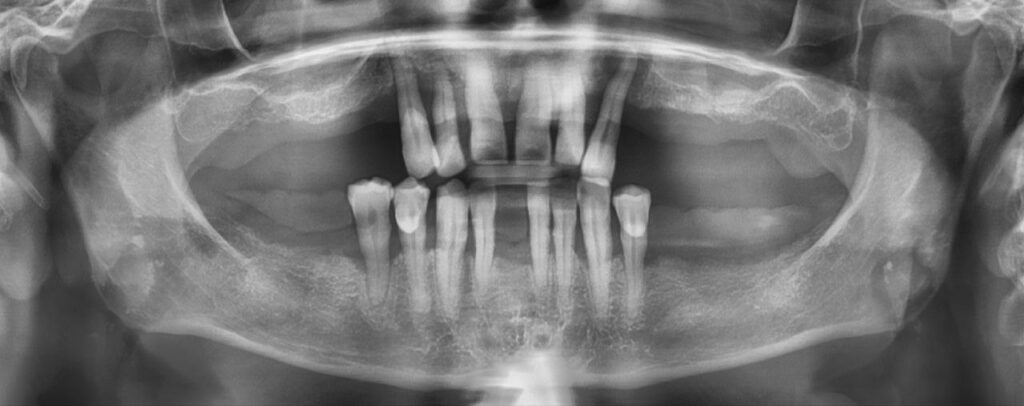

La tomografia 3D ci consente di pianificare ogni intervento con massima precisione e sicurezza.